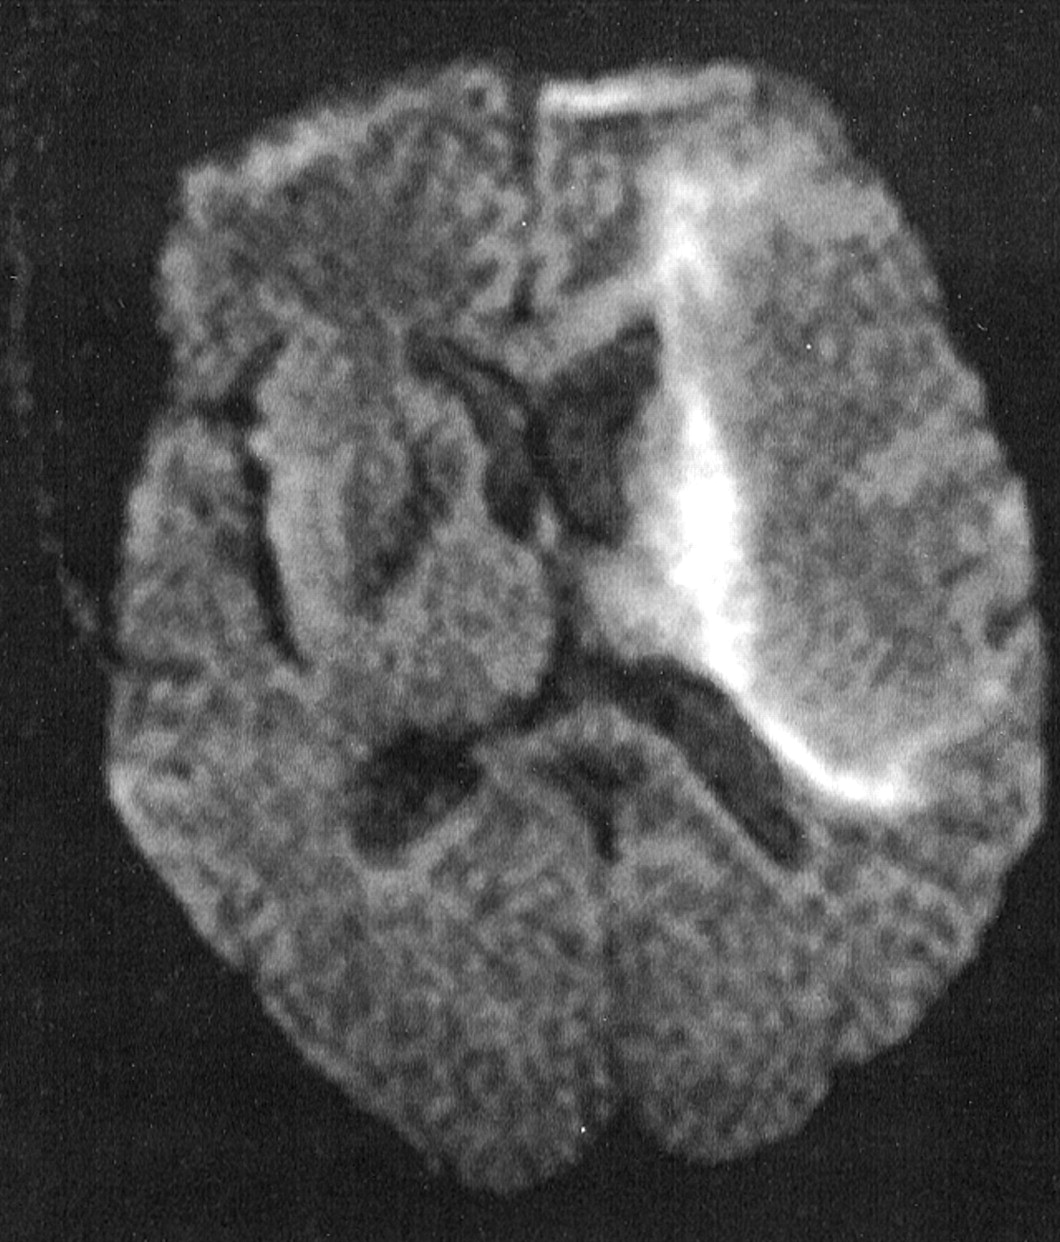

串行MRI显示扩大面积在T1和t2加权像上hyperintensity hypointensity左顶叶。病变主要白质和没有质量效应有关。rim的高信号出现在左顶叶病变边缘的diffusion-weighted图像(图)降低表观扩散系数(ADC) ADC地图。没有IV钆增强后管理。

PML对系统性红斑狼疮治疗免疫抑制是少见。1核磁共振成像发现PML通常包括限制主要病变在白质没有质量效应和对比度增强。1、2⇓先生序列表明发展区域周围的细胞毒性水肿之前白质损伤的区域。2